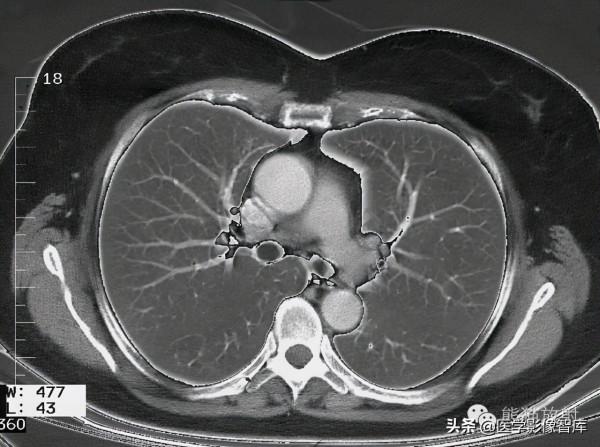

胸部